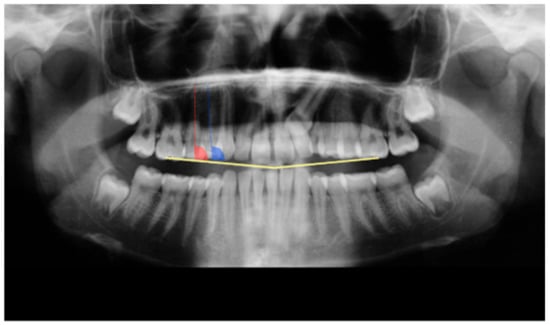

| Landmarks | Definition |

|---|---|

| U6 Fossa | Central fossa of upper first molars right (R) and (L) |

| OB | Point of contact of upper with lower incisors |

| U3 Apex | Apex of upper canine right (R) and (L) |

| U3 Occlusal | Most anterior and lower point of the pulp chamber of the upper canine right (R) and (L) |

| U4 Apex | Apex of upper first premolar right (R) and (L) |

| (when two roots vestibular root apex) | |

| U4 Occlusal | Most anterior and lower point of the pulp chamber of the upper first premolar right (R) and (L) |

| U5 Apex | Apex of upper second premolar right (R) and (L) |

| U5 Occlusal | Most anterior and lower point of the pulp chamber of the upper second premolar right (R) and (L) |

| U1, U2, U3, U4, U5, U6 | Midpoint of Facial Axis Clinical Crown of all the maxillary teeth |